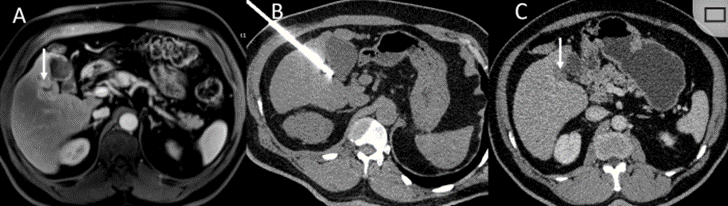

冷凍消融膽囊附近腫瘤病灶

(A)動脈期 MRI 顯示膽囊附近有外周增強病變(箭頭)。

(B)手術(shù)過程中 CT 顯示冷凍探針位于病灶內(nèi)。

(C)消融后,術(shù)后 1 個月CT 顯示完全消融(箭頭)。